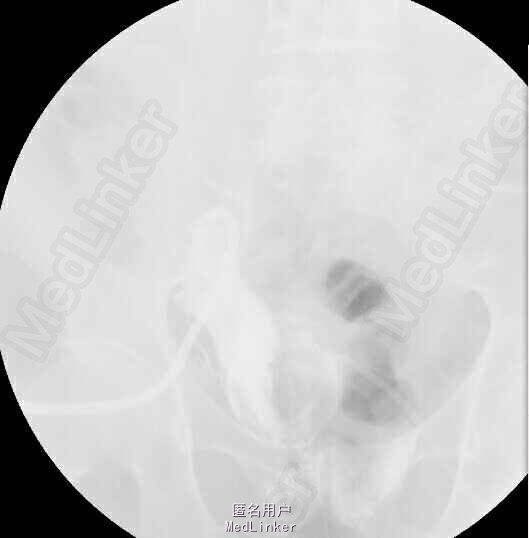

术后病理示:(膀胱肿物)形态学可符合高级别尿路上皮癌,鉴于送检组织表浅且破碎,并于2015-xx全麻下行“腹腔镜根治性膀胱切除术+原位回肠新膀胱术”,腹腔镜下根治性切除膀胱并行双侧盆腔淋巴结清扫,并行回肠原位新膀胱,术后恢复满意,各管道引流通畅,术后病理示:(膀胱肿物)高级别浸润性尿路上皮癌,癌组织浸润粘膜固有层,盆腔淋巴结均未见癌转移。术后复查膀胱造影示:代膀胱充盈良好;代膀胱-尿道吻合口处少许造影剂。拟带管出院。患者术后恢复良好无发热,腹胀、腹痛,饮食、睡眠正常。留置右肾单J管、膀胱造瘘管、左侧盆腔引流管及尿管引流通畅。